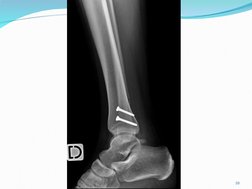

2. sindesmosis:

El tejido conectivo fibroso est presente en

mucha mayor cantidad que en las suturas.

La unin no es tan rgida.

Se forma una membrana o ligamento

interseo.

Tiene ligera movilidad y flexibilidad, gracias a

la pequea separacin entre los huesos y al

ligamento interseo.

Desde el punto de vista funcional son

anfiartroisis.